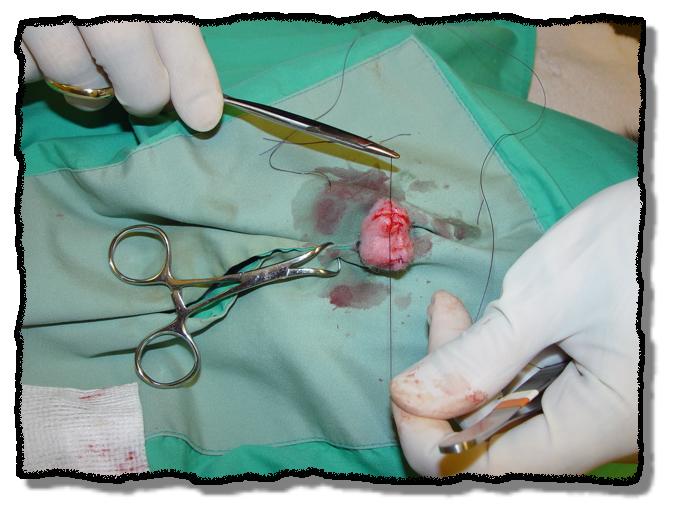

NEUTERING A MALE POSSUM

Skin incision made over each testis. (Note: procedure repeated on opposite side)

Ligamentous attachments to the testis are freed and the vasculature is isolated.

Double-ligation of the testicular vessels.

Skin incision closed with a single subcutaneous cruciate stitch.